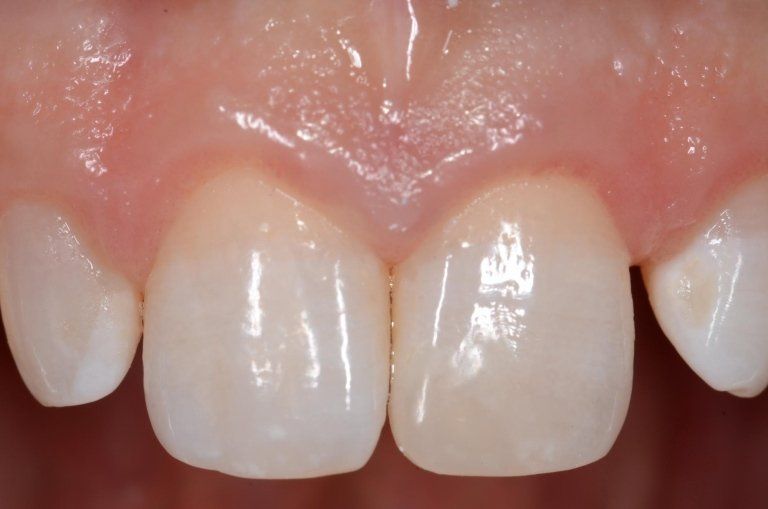

I denti da latte traumatizzati più spesso vanno incontro a necrosi con conseguente cambiamento di colore, divenendo grigiastri, segno della morte delle cellule della polpa dentaria. In altre occasioni, il dente può fratturarsi in maniera più o meno ampia: se il frammento viene ritrovato, potrà essere re-incollato in maniera invisibile, oppure verrà ricostruito con i materiali compositi.